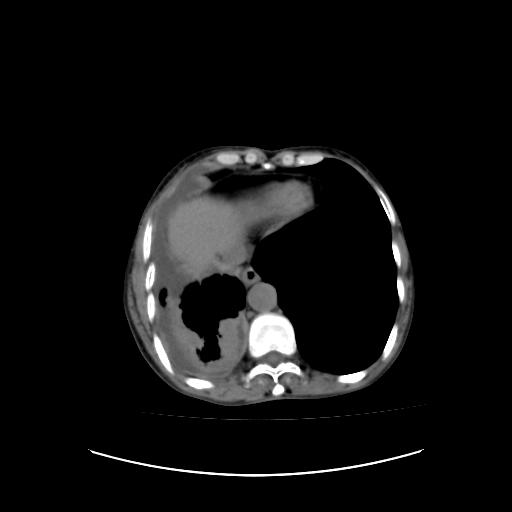

标题: CT16930:女 59 胸痛6个月 胸水脱落细胞学见瘤细胞 [打印本页]

可见多发肺内病灶,且胸膜病灶较多有圆球状而非丘状,多考虑胸膜转移瘤伴胸腔积液,右侧胸廓缩小固定,且部分病灶呈丘状,尚不除外恶性胸膜间皮瘤伴肺内转移

右侧胸膜增厚,局部呈结节状增厚,右侧胸腔少量积液。双肺未见确切肿块影。纵隔未见淋巴结肿大。气管、支气管通畅。考虑右侧胸膜间皮瘤(恶性?)可能性大。不除外癌性胸膜炎。

恶性胸膜间皮瘤伴肺内转移可能性大;或胸膜、肺内均为转移瘤,左肺下叶亦见多发小结节影。

右侧胸廓塌陷,右侧胸膜广泛增厚并见多发胸膜结节,右侧少量胸腔积液并包裹。

右侧广泛胸膜增厚,局部呈结节状增厚,右侧胸腔少量积液。双肺未见确切肿块影。纵隔未见淋巴结肿大。气管、支气管通畅。考虑右侧胸膜间皮瘤(恶性?)可能性大。支持!

右侧胸膜转移瘤,原发灶可能就在在右肺,另外建议检查右侧乳腺.

右胸腔结节均考虑来自胸膜(部分来源于叶裂),考虑胸膜间皮瘤或转移瘤.